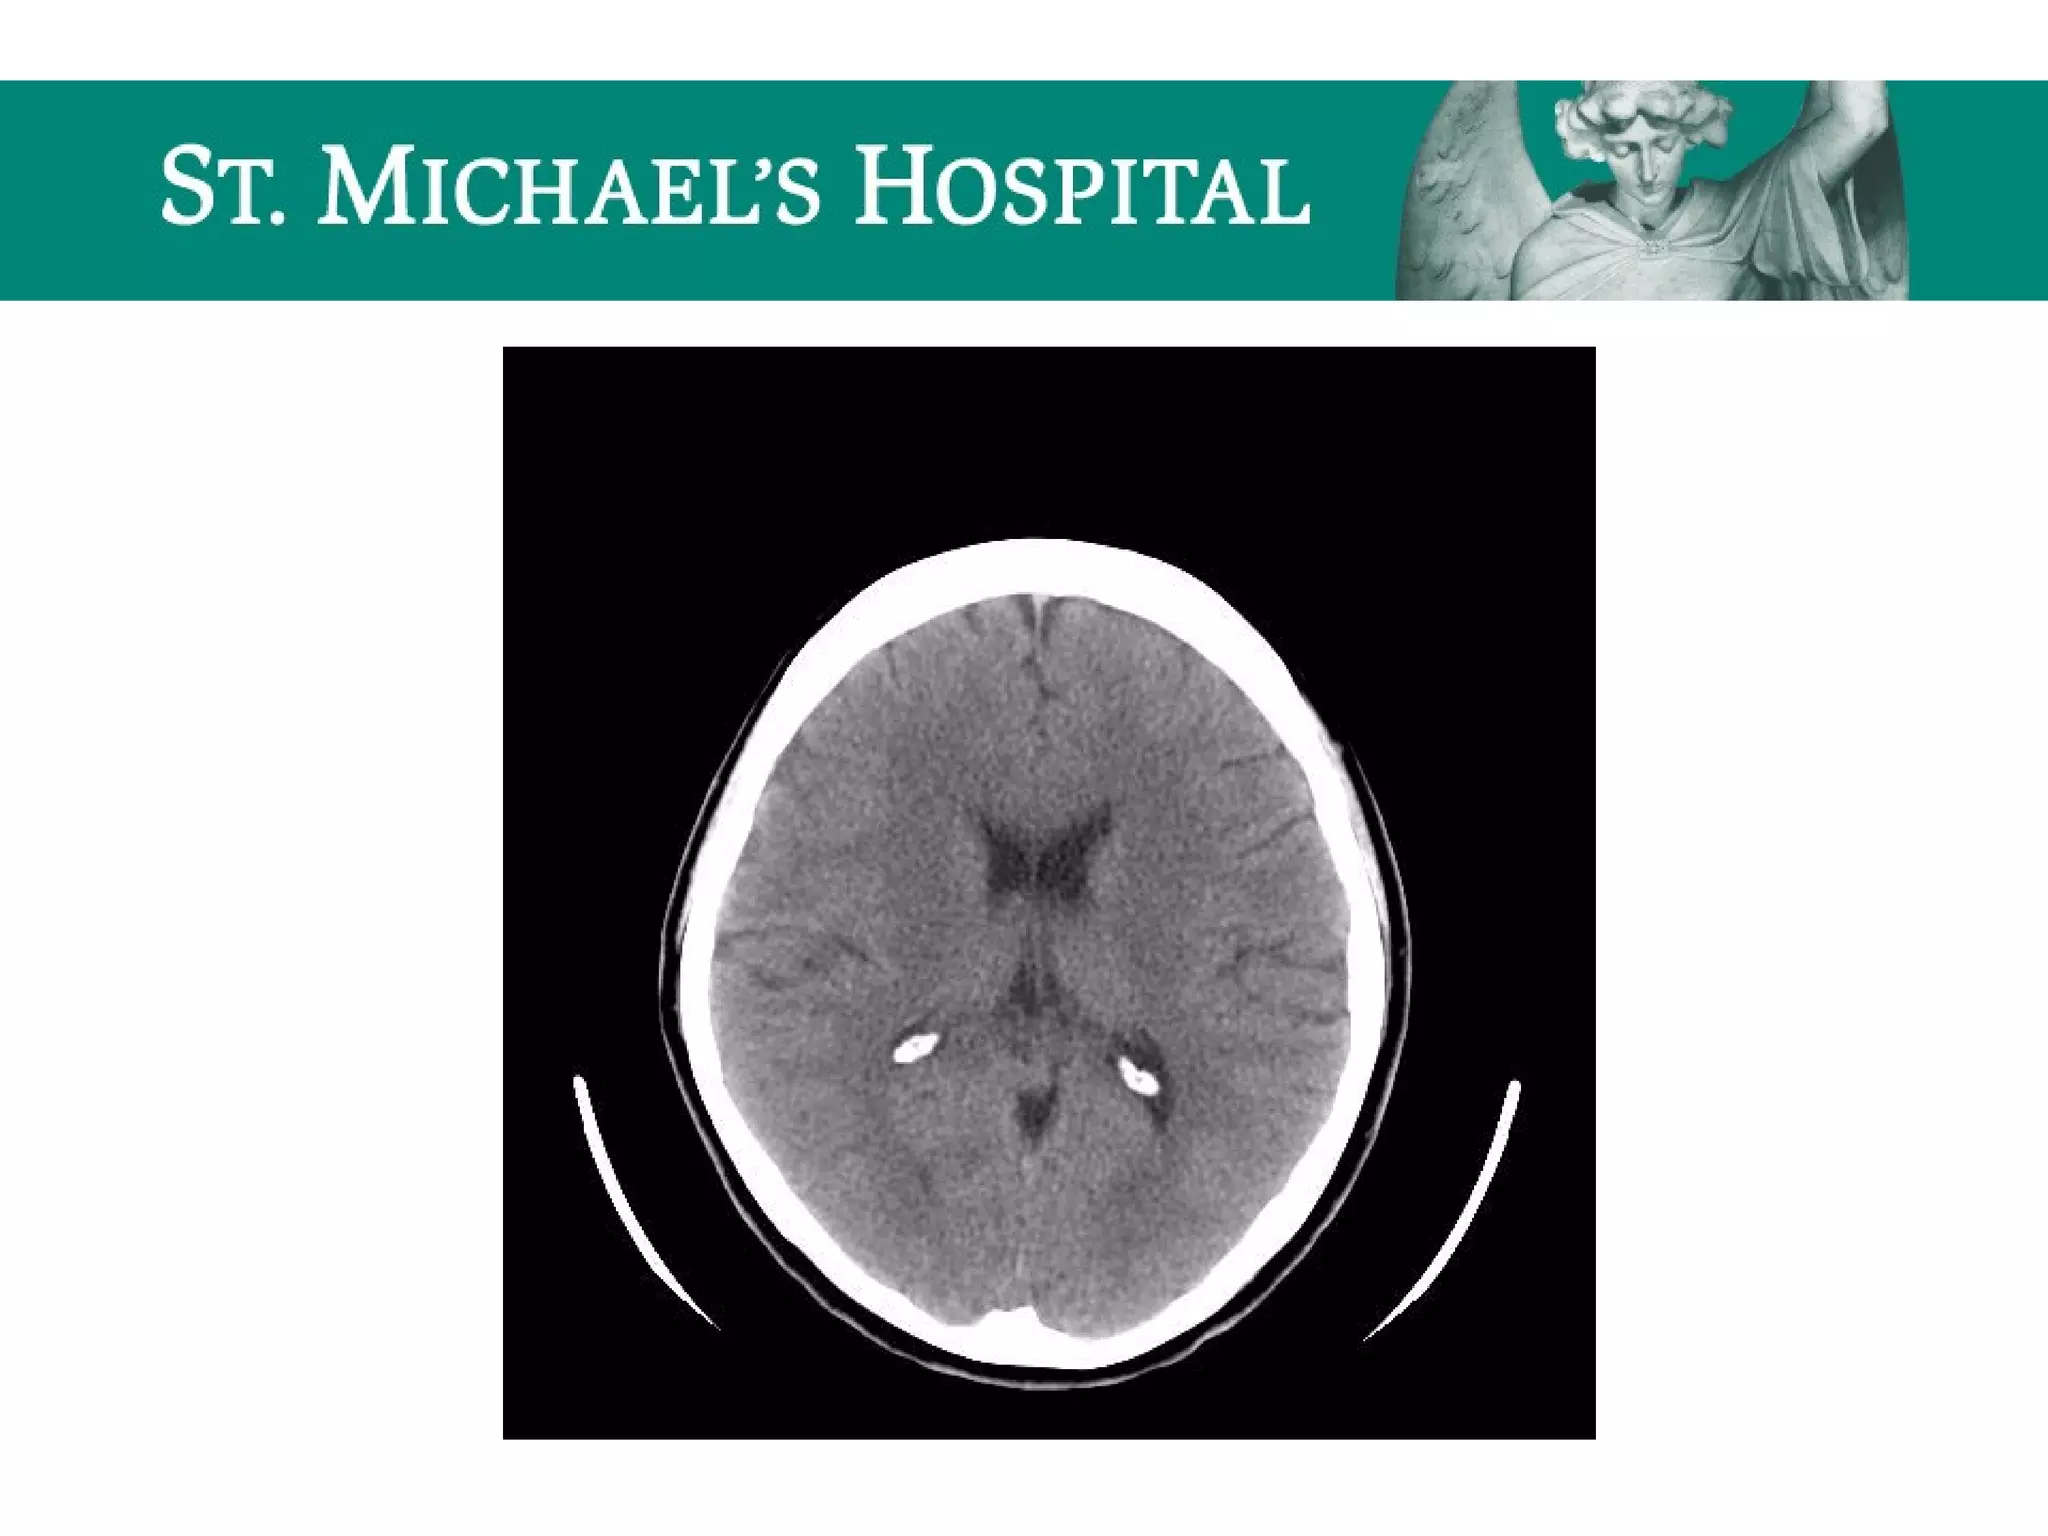

Calcifications

 Falx cerebri/dura

 Choroid plexus

 Pineal gland

 Basal ganglia

Calcifications  Falx cerebri/dura Choroid plexus  Pineal gland  Basal ganglia